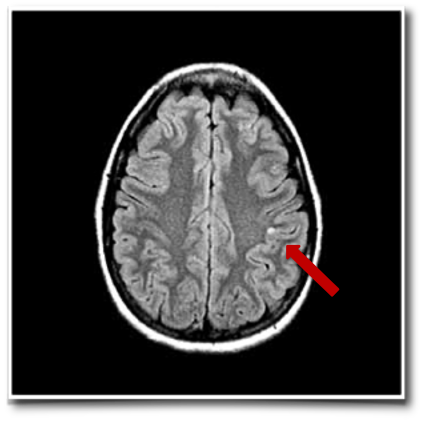

检查结果明确显示,琳娜的癫痫发作存在明确病因——其大脑顶叶区域一处微小的囊性病变,被确认为导致癫痫反复发作的致痫核心。进一步通过脑磁图(MEG)追踪脑功能信号,在负责躯体感觉的中央后回区域,捕捉到了清晰的异常癫痫样放电活动。

顶叶是大脑中处理躯体感觉、空间定位及部分高级认知功能的关键区域。当顶叶出现结构性或功能性病变(例如肿瘤、囊肿、发育异常或损伤后瘢痕等),可能干扰局部神经元的正常电活动,引发异常的同步化放电。这种异常电信号若扩散至邻近的运动皮层或边缘系统等结构,便可诱发感觉性、运动性甚至复杂部分性癫痫发作,其具体临床表现与病变的精确位置及累及范围密切相关。